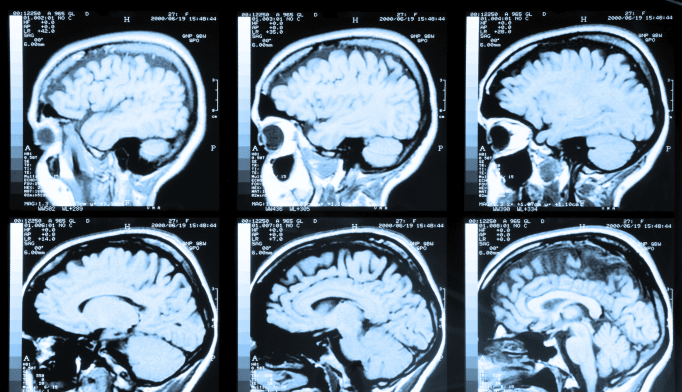

Alzheimer’s Disease (AD) is a progressive neurological disorder that gradually erodes memory and cognitive abilities, eventually impairing the ability to carry out the simplest tasks. Caregivers, family members, and healthcare professionals need to understand the stages of Alzheimer’s to provide appropriate care and support. This article delves into the various stages of Alzheimer’s, highlighting the key characteristics, impacts on daily life, and effective strategies for managing each stage. By comprehending these stages, caregivers can better prepare for the challenges ahead and ensure that individuals with Alzheimer’s maintain the highest quality of life possible.